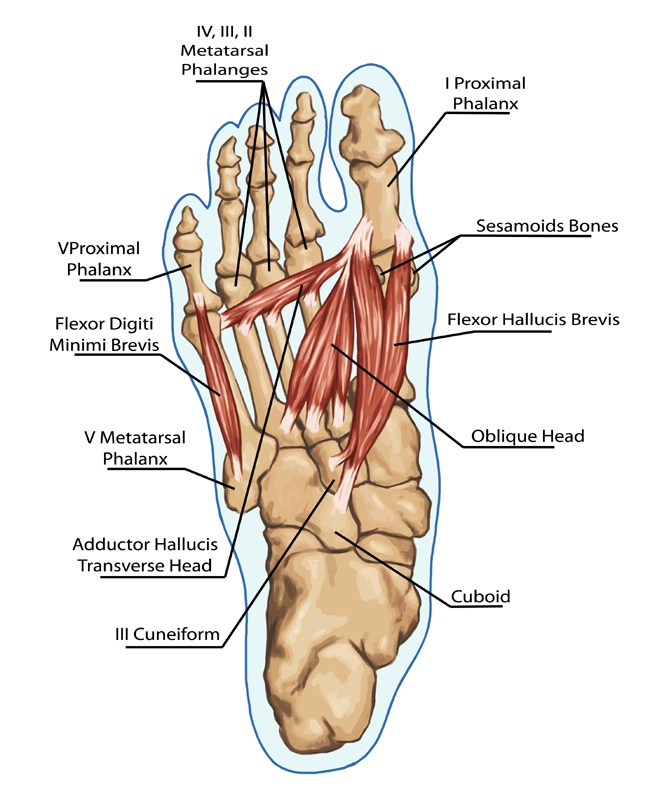

Anatomy Nugget: Why the Feet Are So Important

The feet contain over 7,000 nerve endings and a huge number of mechanoreceptors — tiny sensory structures that detect pressure, vibration and movement.

This is called proprioception, and it is one of the reasons stimulation of the feet can influence relaxation, posture and stability.